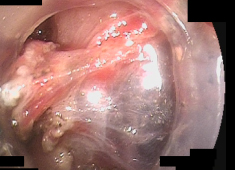

近年、新しい内視鏡の機器が開発され、内視鏡的粘膜下層剥離術(ESD)という新しい内視鏡治療が可能になりました。ESDはITナイフという特殊な電気メスを用いて粘膜下層を剥離できるためEMRでは対応できなかった2cm以上の広い範囲の早期胃がんにも対応でき、より大きな病変の一括した切除ができるようになりました。

内視鏡的に行うため胃を切除することなく病変を切除することができます。

全身麻酔下で行うため手術中の苦痛もありません。